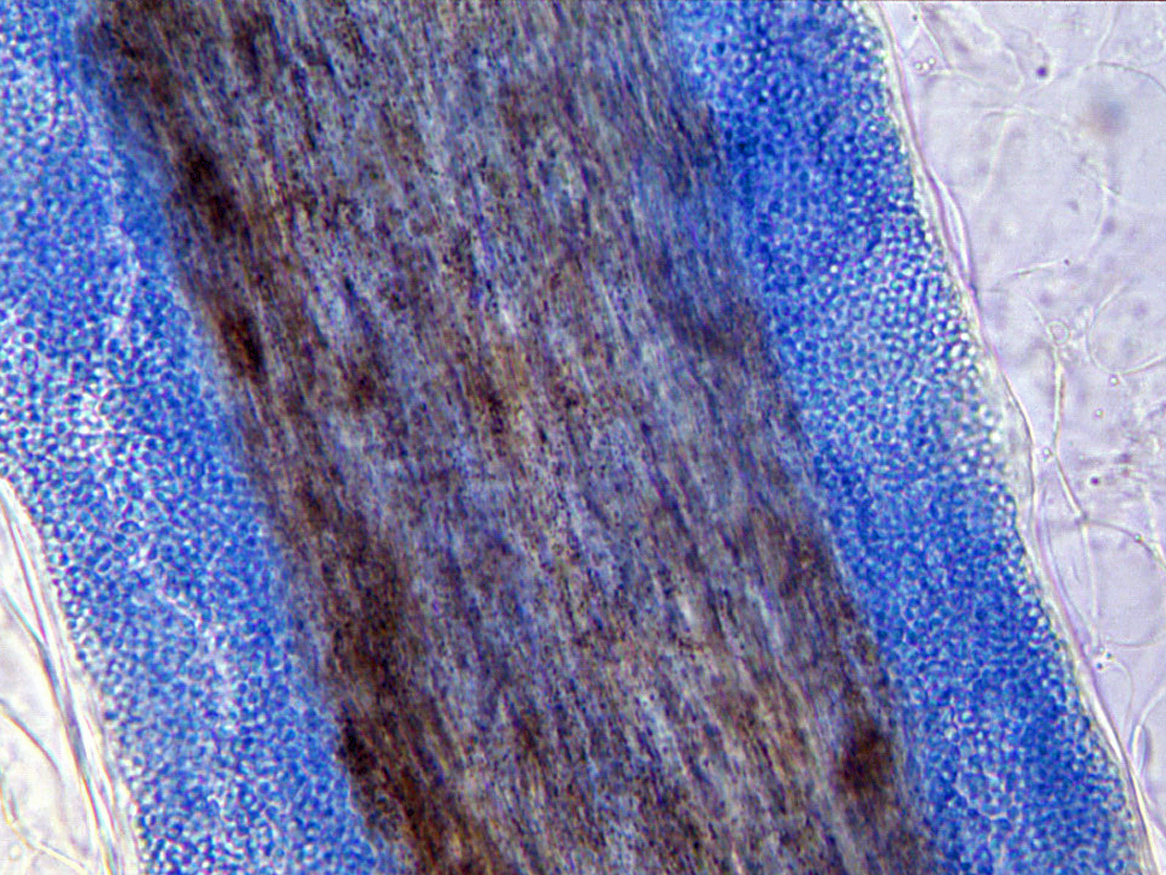

Ectothrix invasion is characterised by the development of arthroconidia on the outside of the hair shaft. The cuticle of the hair is destroyed and infected hairs usually fluoresce a bright greenish yellow colour under Wood's ultraviolet light. Common agents include Microsporum canis, Nannizzia.gypsea, Trichophyton equinum and T. verrucosum.

Endothrix hair invasion is characterised by the development of arthroconidia within the hair shaft only. The cuticle of the hair remains intact and infected hairs do not fluoresce under Wood's ultraviolet light. All endothrix producing agents are anthropophilic eg Trichophyton tonsurans and T. violaceum.